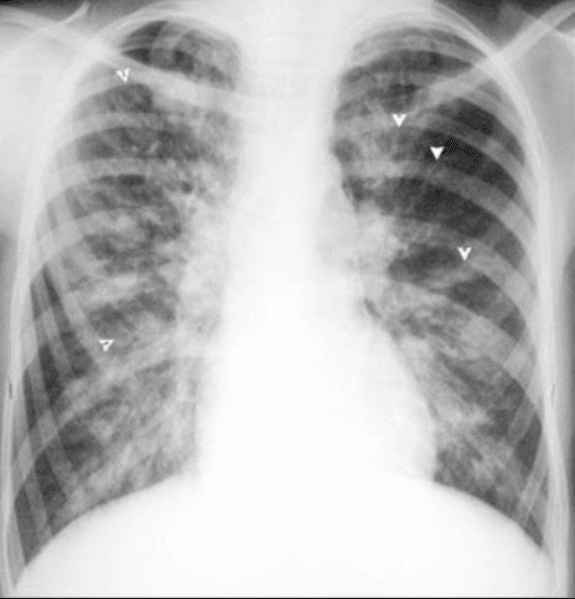

- Trên phim X quang phổi chuẩn: có thể thấy các dấu hiệu gợi ý hoặc khẳng định chẩn đoán giãn phế quản trong một số trường hợp giãn phế quản nhiều và nặng. Tuy nhiên chẩn đoán xác định giãn phế quản thường phải dựa vào phim chụp cắt lớp vi tính lớp 1mm, độ phân giải cao

Hình ảnh giãn phế quản trên X quang:

- Thành phế quản tạo thành các đường song song (đường ray).

- Thể tích của thuỳ phổi có giãn phế quản nhỏ lại, các đường mờ mạch máu phổi xít lại với nhau nếu có xẹp phổi.

- Có các ổ sáng nhỏ giống hình ảnh tổ ong, có thể có ổ sáng với mực nước ngang kích thước thường không quá 2 cm

- Hình ảnh viêm phổi tái diễn vào mùa lạnh xung quanh khu vực giãn phế quản.

- Các đám mờ hình ống biểu hiện của các phế quản bị lấp đầy chất nhầy, mủ.

- Khoảng 7 - 30% trường hợp chụp phổi chuẩn không thấy gì bất thường.